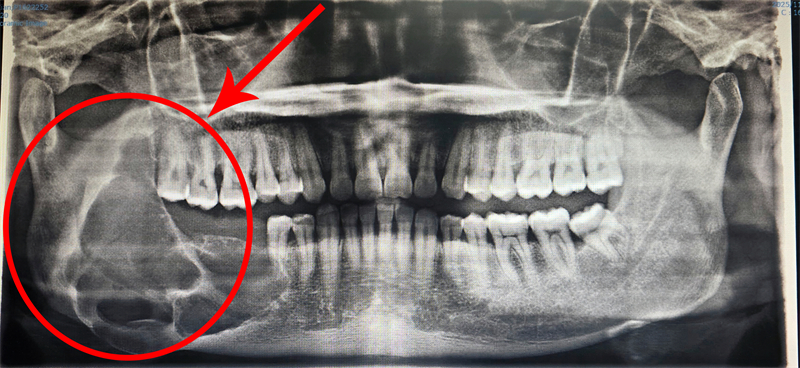

口腔頜面外科陳裕聰副主任醫師接診后,第一時間感受到患者的焦慮與無助,當即安排全面影像學檢查。檢查結果顯示,成釉細胞瘤已然復發,病變范圍大幅擴大,右下頜骨升支遭嚴重破壞,若拖延治療,不僅會導致面部畸形,更會造成不可逆的功能障礙。

深知患者的迫切需求,手術團隊反復研讀影像報告,結合患者身體狀況反復推演,最終量身定制“數字化手術導板+腓骨移植”的個性化治療方案。